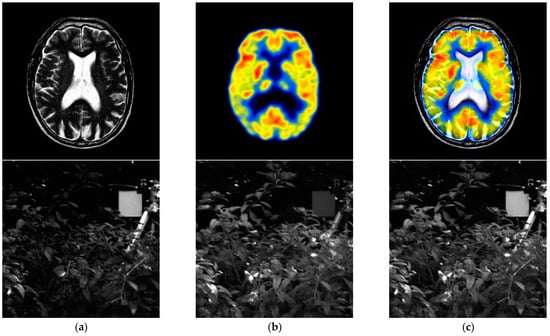

We conducted a comprehensive analysis of the impact of NSST decomposition levels on image fusion performance and found that increasing the number of decomposition levels appropriately significantly improved the image fusion results. Our proposed multi-focus image fusion model based on NSST was thoroughly validated through simulation experiments. When compared to traditional and deep-learning-based algorithms, our method exhibited substantial advantages in terms of preserving edge details and effectively utilizing complementary image information, as indicated by both subjective and objective evaluation criteria. However, despite these remarkable achievements, there are still certain limitations that warrant further investigation. Notably, the average gradient metric of our algorithm did not reach its optimal value, although it remains competitive with other approaches. As a result, our next step involves delving deeper into enhancing the average gradient information of the fused images. Figure 13 showcases the fusion results of our algorithm applied to medical images, infrared and visible images. For anatomical and functional image fusion, we utilized the RGB to YUV color space conversion, where the Y channel of the functional image was fused with the anatomical image using our proposed algorithm. Subsequently, the YUV to RGB space conversion was applied to obtain the final fusion result. The results demonstrate the effectiveness of our algorithm in achieving information complementarity.

Figure 13.

Other multi-modal image fusion results. (a) Source 1; (b) source 2; (c) proposed.